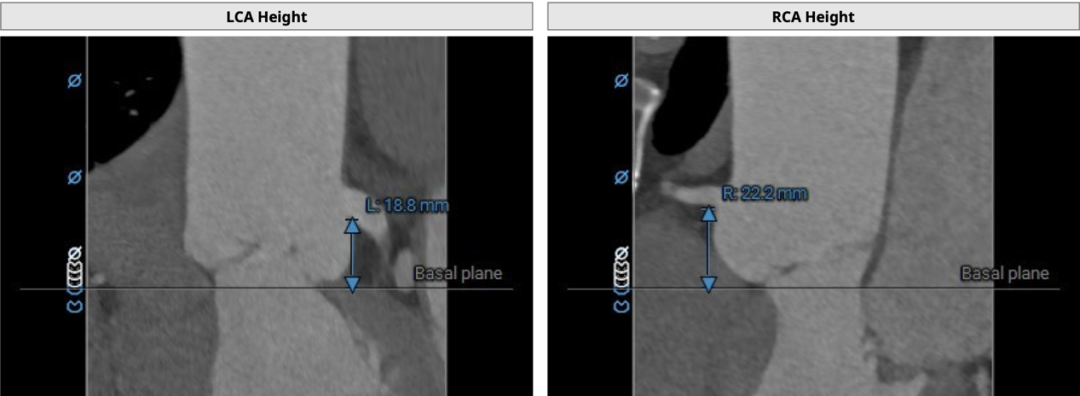

双侧冠脉开口高度可LCA:13.9mm,RCA:21.8mm: